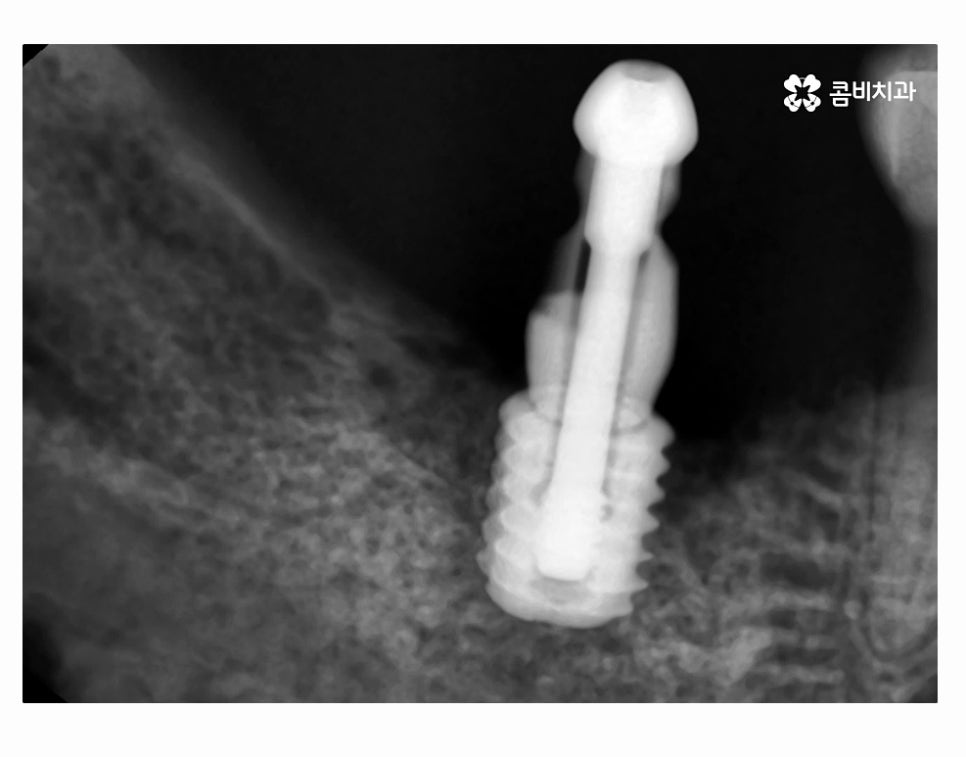

또한 임플란트 시술 후에는 잇몸질환이 발생하지 않도록 주의해야 하는데

어금니 발치 후 임플란트를 식립하게 되면 신경이 없기 때문에

통증에 무감각해질 수 있기에 통증이나 불편함이 느껴지지 않더라도

꼭 주기적으로 치과 검진을 받는 것이 임플란트 수명을 잘 유지하고

부작용을 예방할 수 있는 방법이라고 할 수 있는데요.

어금니 발치 후 임플란트를 건강하게 식립을 한 후에는

임플란트의 저작력은 자연치아에 버금갈 정도로

우수한 편이기 때문에 치아 상실로 인한 불편함은

많은 부분 해소될 수 있지만 보다 오랜 수명을 유지하기 위해서는